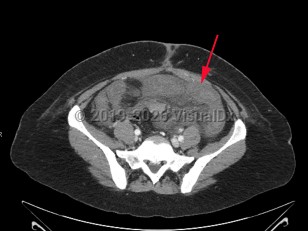

Acute mesenteric ischemia is a sudden interruption or severe reduction in blood flow to the bowel leading to ischemia, necrosis, and ultimately perforation. It is a medical emergency requiring emergent intervention to restore perfusion, often requiring a multidisciplinary approach. Mesenteric ischemia can result from several distinct pathologic entities including embolic disease, arterial thrombosis, mesenteric vein thrombosis, and lack of perfusion due to low flow states or nonocclusive mesenteric ischemia (NOMI).

Embolic disease most commonly affects the superior mesenteric artery (SMA), largely due to anatomic factors. The SMA branches off the aorta at a 45 degree angle, and rapidly tapers, providing a funnel-like shape that traps emboli. The SMA serves a large area of the bowel from the duodenum through the first two-thirds of the transverse colon, producing profound injury in the setting of acute loss of perfusion.